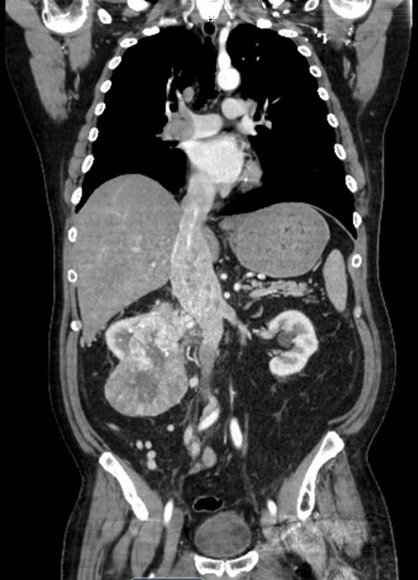

Case description: We present a case of a 65-year-old male who presented to the hospital with syncope, and was subsequently diagnosed with a level four cavoatrial sinus tumor thrombus extending from a primary renal mass. The patient had no concerning physical exam and electrocardiogram (EKG) findings, however, transthoracic and transesophageal echocardiography revealed severely reduced systolic function with a hyperechoic, vascular, and cystic mass extending from the IVC into the right atrial cavity that originated from a renal mass that involved the right renal vein and IVC.